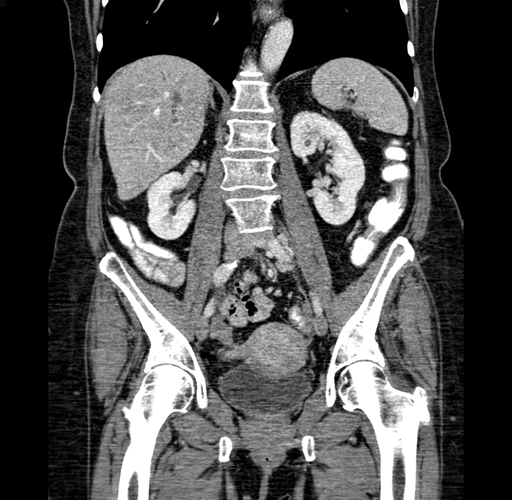

Pre-Chemo: Coronal Venous

Coronal Venous